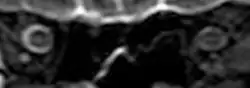

The third case of visual changes while on board the ISS had no changes in visual acuity and no complaints of headaches, transient visual obscurations, diplopia or pulsatile tinnitus during the mission. Upon return to Earth, no eye issues were reported by the astronaut at landing. Fundus examination revealed bilateral, asymmetrical disc edema. There was no evidence of choroidal folds or cotton-wool spots, but a small hemorrhage was observed below the optic dics in the right eye. This astronaut had the most pronounced optic-disc edema of all astronauts reported to date, but had no choroidal folds, globe flattening or hyperopic shift. At 10 days post landing, an MRI of the brain and eyes was normal, but there appeared to be a mild increase in CSF signal around the right optic nerve.[5]

The sixth case of visual changes of an ISS astronaut was reported after return to Earth from a 6-month mission. When he noticed that his far vision was clearer through his reading glasses. A fundus examination performed 3 weeks postflight documented a grade 1 nasal optic-disc edema in the right eye only. There was no evidence of disc edema in the left eye or choroidal folds in either eye (Figure 13). MRI of the brain and eyes days postflight revealed bilateral flattening of the posterior globe, right greater than left, and a mildly distended right optic nerve sheath. There was also evidence of optic-disc edema in the right eye. A fundus examination postflight revealed a "new onset" cotton-wool spot in the left eye. This was not observed in the fundus photographs taken 3 weeks postflight.[5]